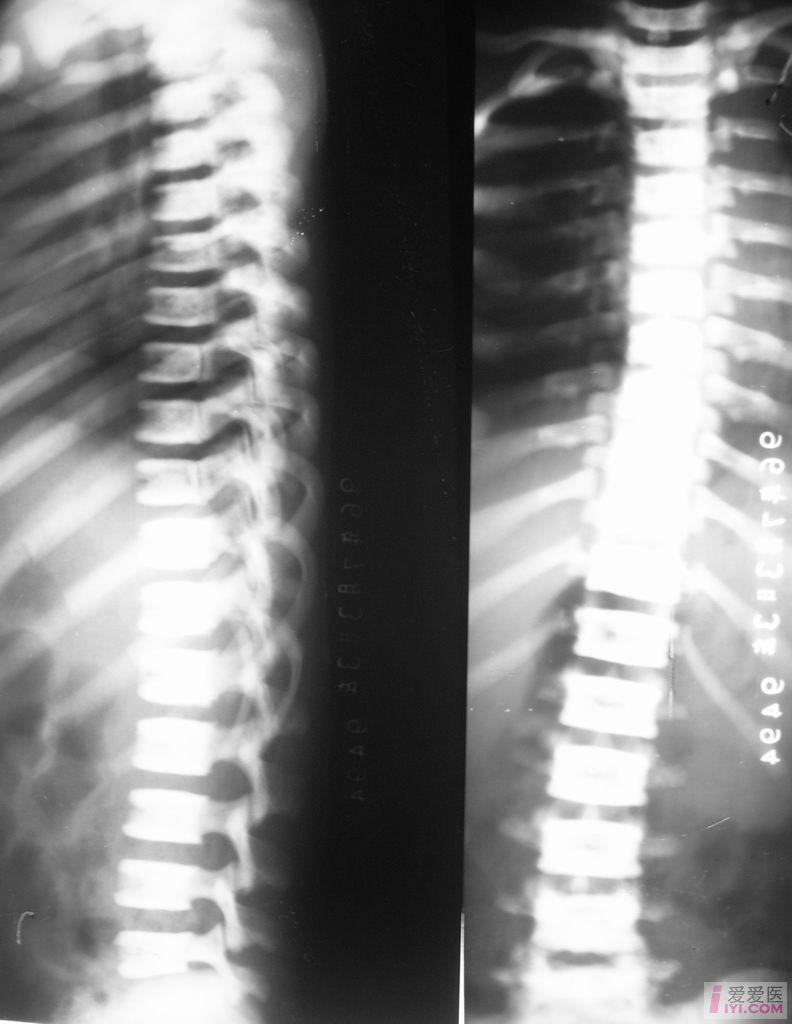

【原创】石骨症 - 医学影像学讨论版 - 爱爱医医学论坛

图片尺寸792x1024